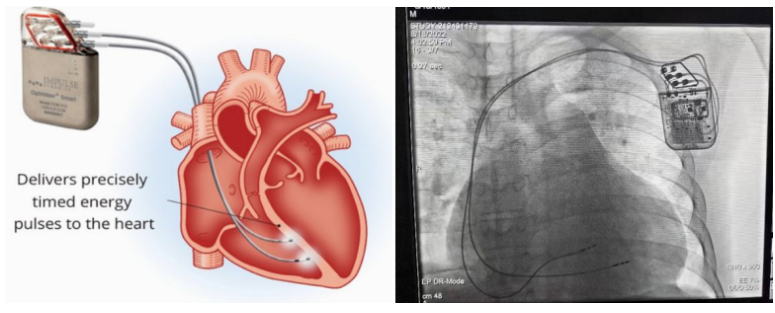

①植入式心臟復(fù)律除顫器

Implantable Cardioverter Defibrillator,ICD

植入式心臟復(fù)律除顫器是一種具有除顫功能的高級(jí)起搏器,是一種體積小、能植入患者胸部皮下組織的醫(yī)療設(shè)備。慢性心衰患者易發(fā)生室性心動(dòng)過(guò)速或心室顫動(dòng),導(dǎo)致心源性猝死(SCD)。ICD 則能在幾秒內(nèi)自動(dòng)識(shí)別并治療快速室性心律失常,通過(guò)低能量心臟轉(zhuǎn)復(fù)和高能量除顫等功能,顯著降低惡性室性心律失常引起的猝死風(fēng)險(xiǎn)??杉皶r(shí)自動(dòng)為患者轉(zhuǎn)復(fù)心律,通俗地說(shuō)就是裝在體內(nèi)的自動(dòng)除顫儀。

國(guó)內(nèi)研發(fā)企業(yè):無(wú)雙醫(yī)療、邁瑞、魚(yú)躍、久心、微創(chuàng)、維偉思、麥邦等